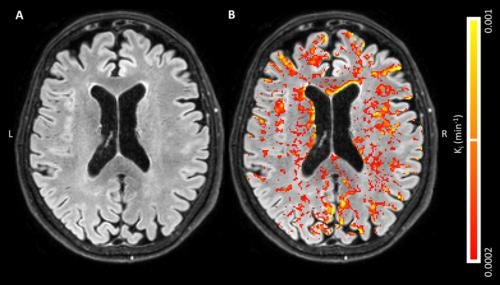

Brain scans revealed "too many white matter lesions" - clear evidence that his brain's tiny blood vessels were starved of oxygen and his neural tissue was under siege.

Brain scans revealing Blood-Brain Barrier leakage: Normal brain tissue (left) vs. areas of leakage shown in red/yellow (right)

You see, your brain is protected by an incredibly sophisticated security system called the Blood-Brain Barrier (BBB). Think of it as a checkpoint that decides what gets into your brain and what stays out.